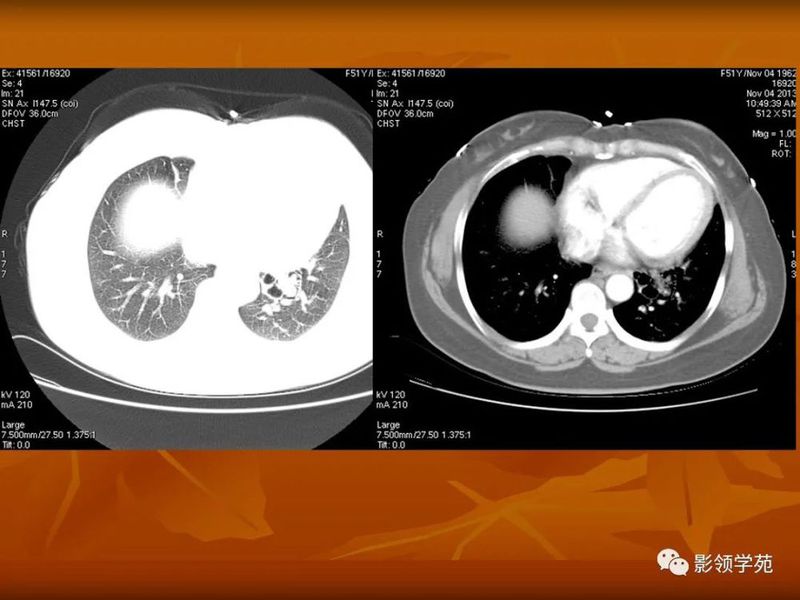

(1)较大含空洞性肿块,洞壁较厚,大于15mm,空洞外壁有分叶、毛刺,洞壁凹凸不平有壁结节,增强可见不规则强化,周围未见明显卫星病灶时,首先考虑周围型肺癌;癌性空洞洞壁一般肺门侧较厚,空洞多偏于外侧,伴有同侧淋巴结肿大更支持肺癌诊断。

(2)空洞病变发生于双肺上叶尖后段、下叶背段,病变周围可见点状、结节状及片状卫星病灶,洞壁组织无明显强化或有包膜线样强化时,考虑结核;结核球的空洞多位于病变的肺门侧,与引流支气管相同,洞内壁一般较光滑。